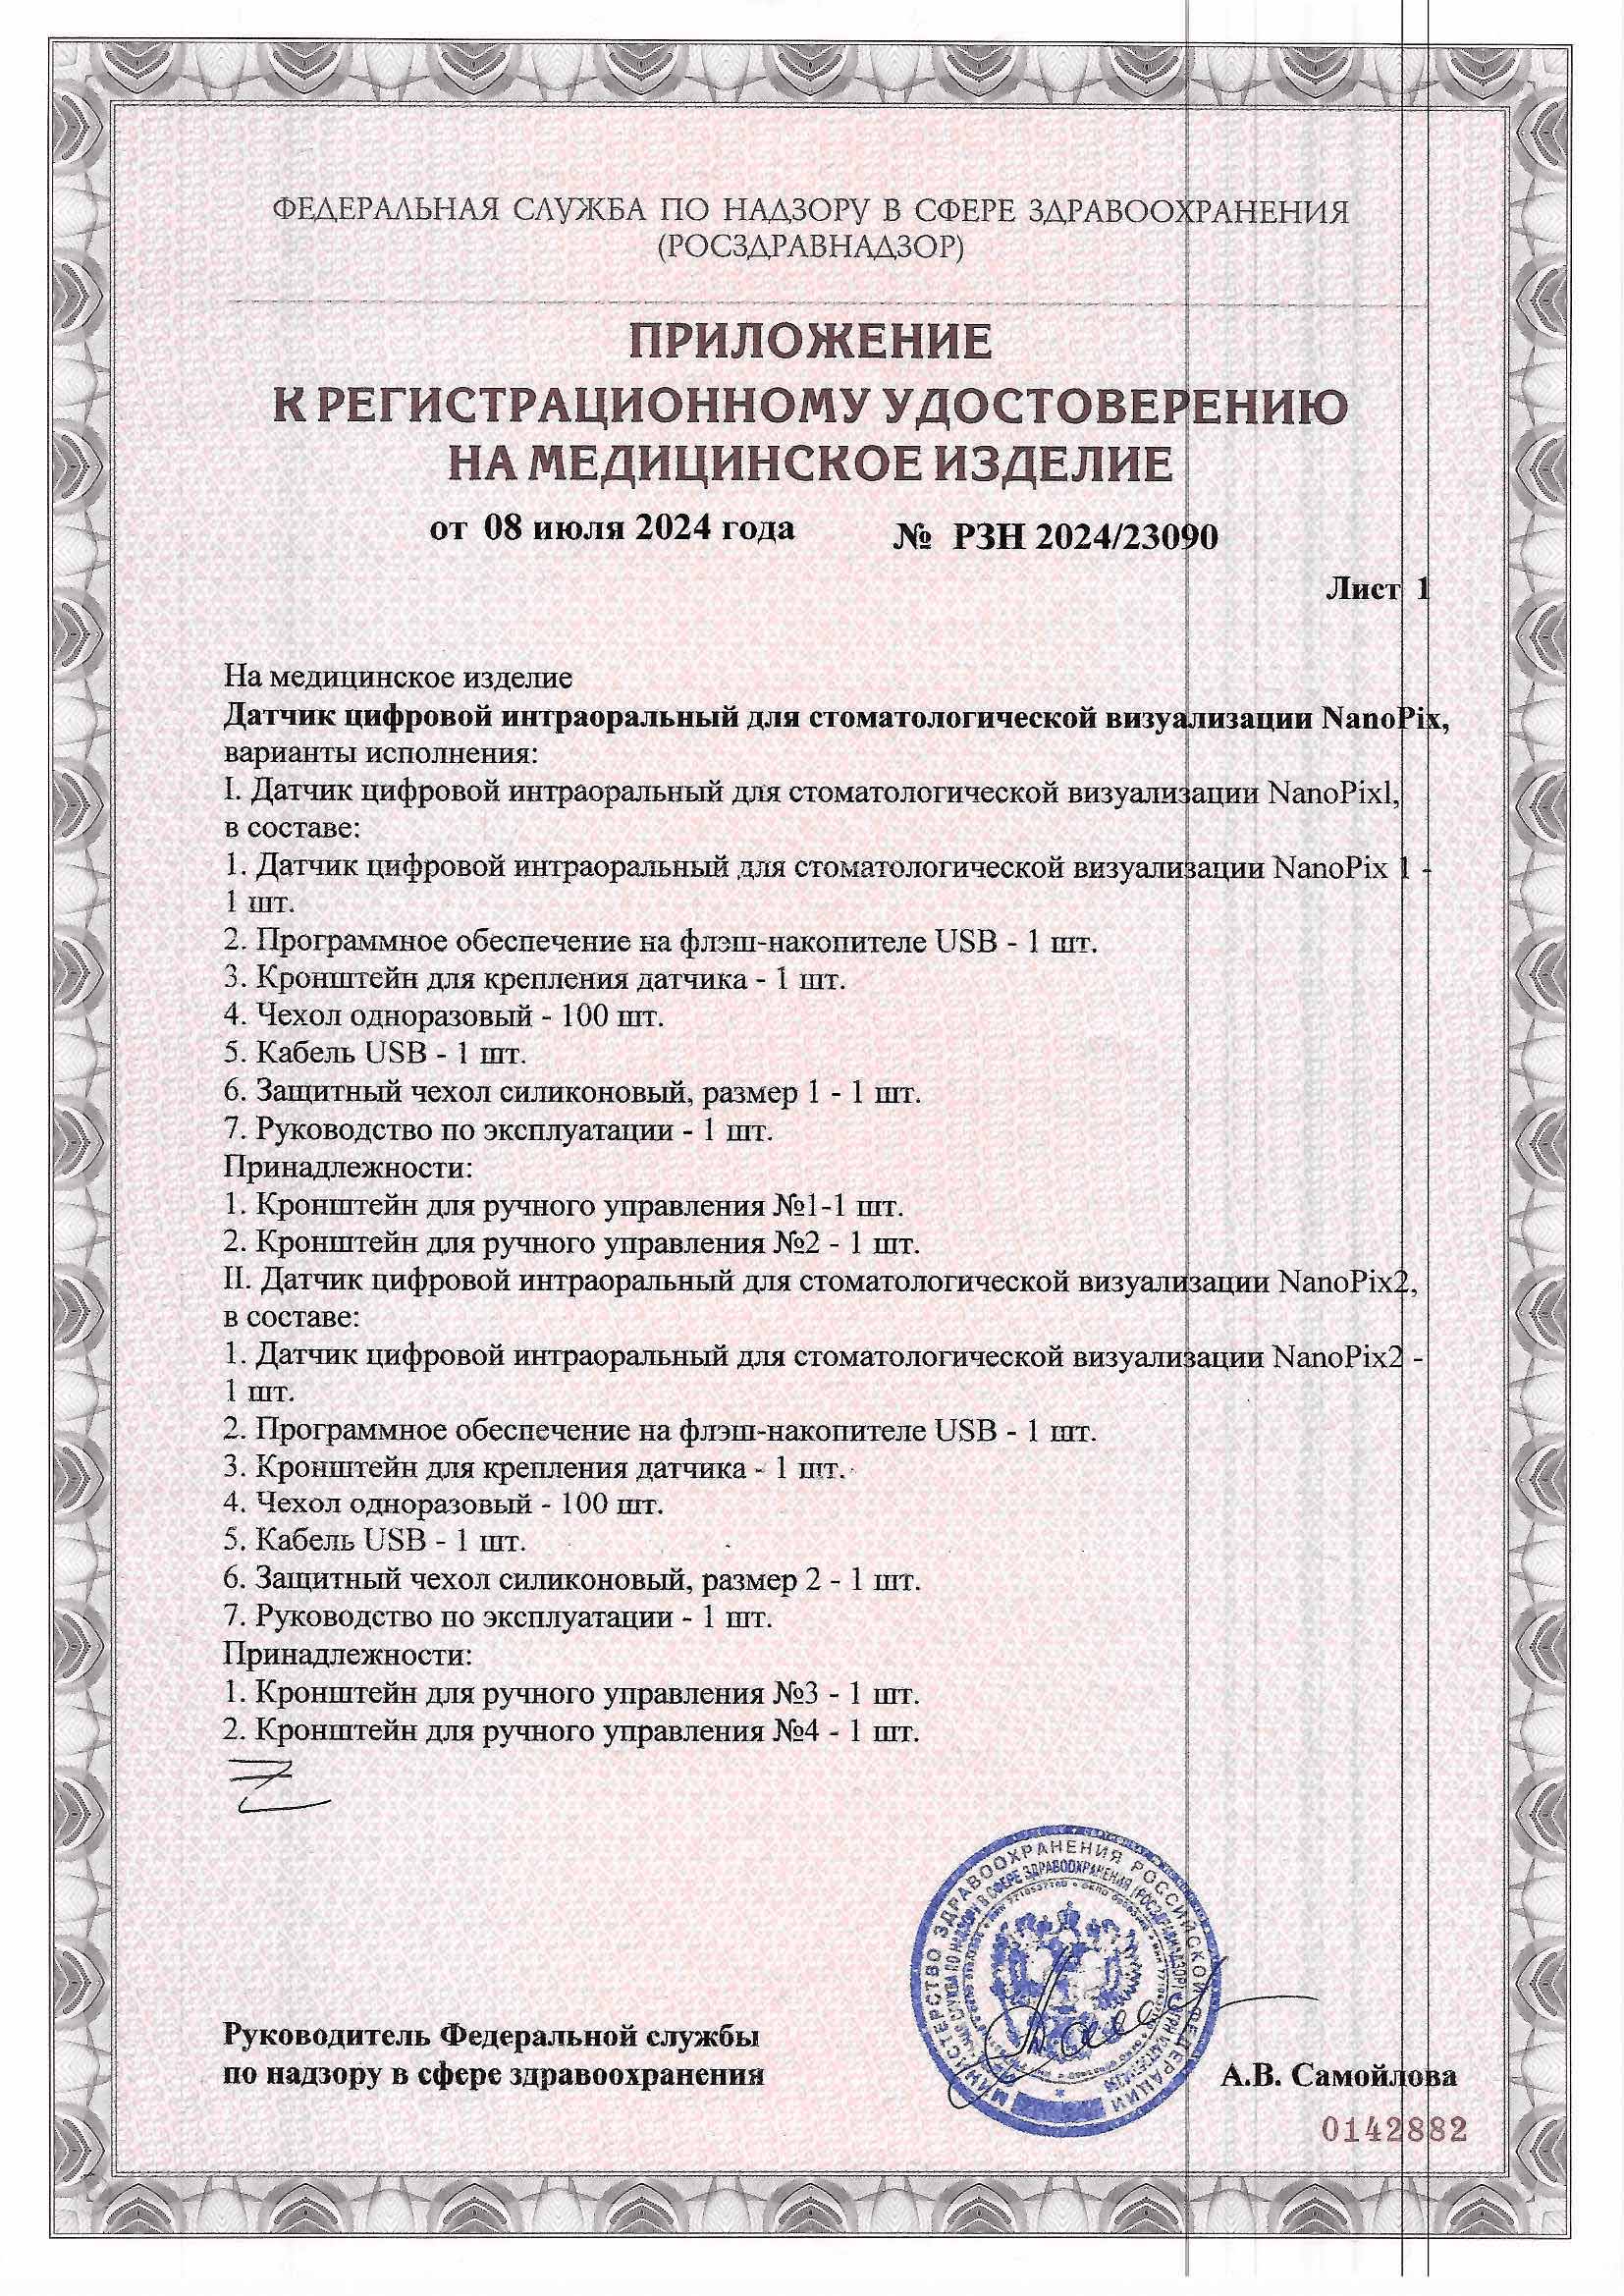

Визиограф NANOPIX с искусственным интеллектом (Nano AI)

Визиограф NANOPIX с искусственным интеллектом (Nano AI)

Автоматическое определение экспозиции. Супертонкий датчик - 4,5 мм. Технология APS CMOS. Более 5000 снимков без потери качества. Разрешение - 25 пар линий/мм.

Визиограф NANOPIX с искусственным интеллектом (Nano AI)

Автоматическое определение экспозиции. Супертонкий датчик - 4,5 мм. Технология APS CMOS. Более 5000 снимков без потери качества. Разрешение - 25 пар линий/мм.